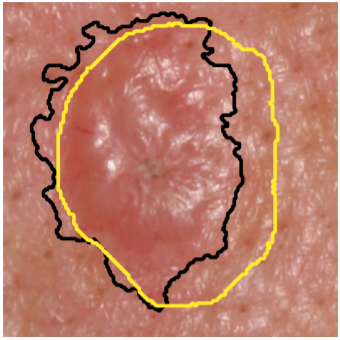

Segmentation Style Discovery: Application to Skin Lesion Images

Kumar Abhishek, Jeremy Kawahara, Ghassan Hamarneh

Medical Image Computing and Computer-Assisted Intervention (MICCAI) ISIC Skin Image Analysis Workshop (MICCAI ISIC), 2024

(Best Paper Award)

StyleSeg learns plausible, diverse, and semantically consistent segmentation styles without annotator correspondence, outperforming competing methods while maintaining alignment with annotator preferences. [Abstract] [BibTeX] [Presentation Slides]

Variability in medical image segmentation, arising from annotator preferences, expertise, and their choice of tools, has been well documented. While the majority of multi-annotator segmentation approaches focus on modeling annotator-specific preferences, they require annotator-segmentation correspondence. In this work, we introduce the problem of segmentation style discovery, and propose StyleSeg, a segmentation method that learns plausible, diverse, and semantically consistent segmentation styles from a corpus of image-mask pairs without any knowledge of annotator correspondence. StyleSeg consistently outperforms competing methods on four publicly available skin lesion segmentation (SLS) datasets. We also curate ISIC-MultiAnnot, the largest multi-annotator SLS dataset with annotator correspondence, and our results show a strong alignment, using our newly proposed measure AS2, between the predicted styles and annotator preferences. The code and the dataset are available on GitHub.